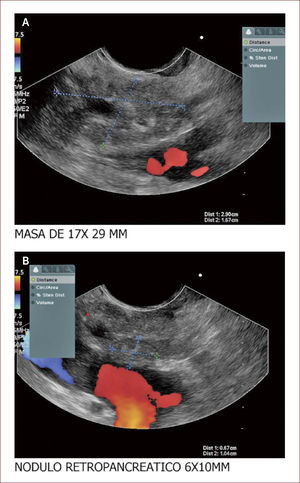

Lesión de cabeza de páncreas en un hombre de 67 años. La lesión es sólido quística. En la imagen de arriba a la izquierda se ve que la lesión mide 30mm es de ecos mixtos y con componente sólido y líquido. En la imagen de arriba a la derecha se ve la vía biliar y la lesión comprimiéndola. En la imagen de abajo a la izquierda se ve la lesión con calcificaciones, nódulos al lado. En la de abajo a la derecha se ve la punción de la que salió material mucoide y algunos fragmentos de tejido que fueron leídos como acinos normales. Por imágenes y por el tipo de lesión se pensó en IPMN. Tiene características quirúrgicas, como son componente sólido en la lesión, quiste mayor de 30mm, nódulos y como se verá en la imagen siguiente un Wirsung mayor de 10mm y tortuoso con nodulaciones.

En esta se ve el Wirsung del mismo paciente dilatado y tortuoso, con nodulaciones y la masa pegada a la porta. El paciente fue llevado en otra ciudad a cirugía por un grupo de Páncreas y se confirmaron los hallazgos anteriores y tenía criterio de no resecabilidad por gran plastrón a nivel portal.